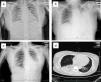

The primary abnormality of all patients on the chest radiograph and CT was patchy or diffuse consolidation in single or multiple lobes. The degree of lung lesions in the pregnant patient was comparable with that in the non-pregnant patients on admission (Fig. 1a–d). Clinical symptoms were improved in all three patients after oseltamivir administration for 6 days, and the hospital days were 13, 11 and 12, respectively (Table 1).

Representative radiographic findings in the pregnant and non-pregnant H7N9 patients. (a) Chest radiograph of case 1 (pregnant) taken on admission, showing bilateral pulmonar patchy high density shadows; (b) Chest radiograph of case 2 taken on admission, showing a patchy, high density shadow in the middle-inferior lobe of the left lung; (c) Chest radiograph of case 3 taken on admission, showing a patchy, high density shadow of the inferior lobe of the left lung; (d) CT scan of case 1 (pregnant) taken on admission, showing significant consolidation of the inferior lobe of the right lung and a patchy, high density area in the inferior lobe of the left lung.